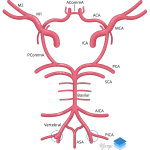

- Ruptured left PICA aneurysm

Discussion

- Kallmes DF, Lanzino G, Dix JE, Dion JE, Do H, Woodcock RJ, Kassell NF. Patterns of hemorrhage with ruptured posterior inferior cerebellar artery aneurysms: CT findings in 44 cases. Am J Roentgenol 1997; 169(4): 1169-1171.